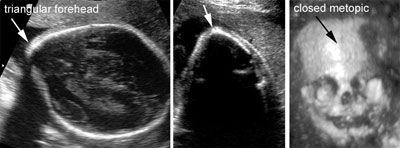

Trigonocephaly

Click the image to magnify it

Legend:An abnormal shape of the skull with a triangular forehead and a premature closure of the metopic suture is suggestive of trigonocephaly, a rare form of craniostenosis that is frequently associated with other anomalies

Reference(s):Chaoui R, Levaillant JM, Benoit B, Faro C, Wegrzyn P, Nicolaides KH. Three-dimensional sonographic description of abnormal metopic suture in second- and third-trimester fetuses. Ultrasound Obstet Gynecol 2005;26(7):761–4. PubMed PMID: 16308900.